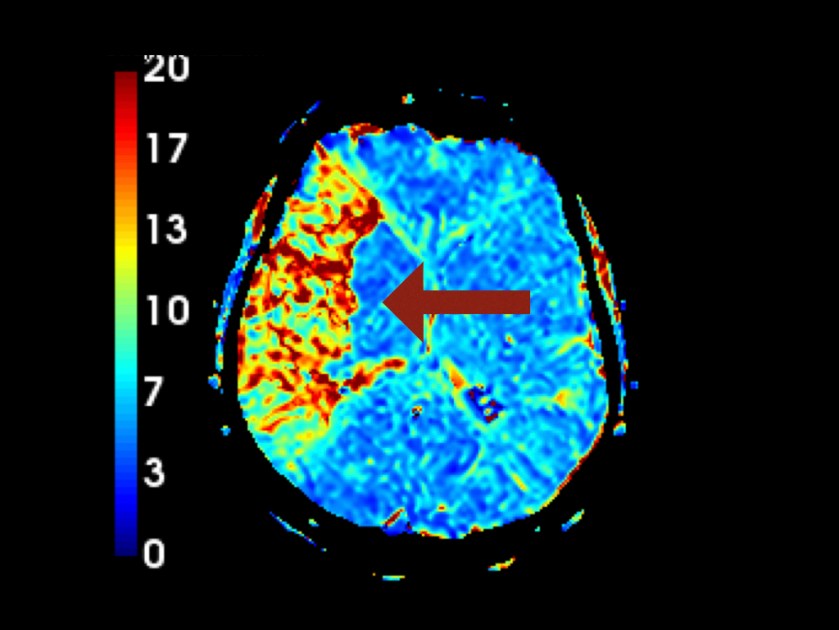

Perfusion:

In der Perfusionssequenz stellt sich bereits eine ausgeprägte Minderperfusion dar. Das Perfusions-Diffusions-Missmatch hat ein großes Volumen = viel potentiell rettbares Hirnparenchym durch rekanalisierende Therapien!